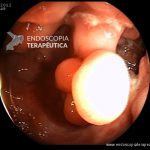

- Doença de Crohn em remissão – pseudopólipos